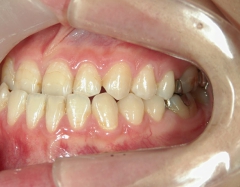

矯正歯科 治療前矯正歯科 治療前

主訴:受け口(反対咬合)を治したい

矯正歯科 治療前 急速拡大装置で上顎を広げた後、ワイヤーへ移行 非抜歯

no.31_7964_治療前_右 .JPGno.31_7964_治療前_正面 .JPGno.31_7964_治療前_左 .JPG